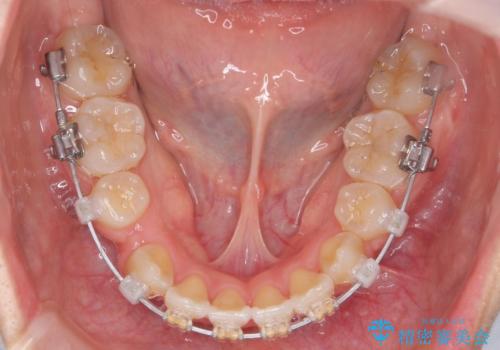

綺麗な歯並びを手に入れられたと同時に、口元もスッキリし、仕上がりに満足いただくことができました。